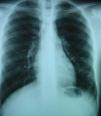

Paciente de 15 años de edad, intervenido mediante técnica de Kasai atípica a los 2 meses de vida por atresia de vías biliares, que presenta hipoxemia progresiva sin otra sintomatología acompañante. En la exploración física destacan acropaquias, uñas en vidrio de reloj y cianosis labial. Auscultación cardiopulmonar normal sin signos de dificultad respiratoria. Hepatomegalia de 2cm. Saturación arterial de oxígeno (SaO2) basal del 88% con ortodesoxia positiva. En la gasometría arterial (con fracción inspiratoria de oxígeno [FiO2] del 21%) se aprecia pH de 7,41, presión parcial arterial de dióxido de carbono (PaCO2) 36,5mmHg, PaO2 53,3mmHg, bicarbonato de 22,7mEq/l y exceso de bases de −1,3mEq/l. Se realiza una espirometría forzada, que es normal y una radiografía de tórax en la que se aprecia una condensación en el lóbulo inferior izquierdo. En la ecocardiografía se observa un corazón estructuralmente normal y, tras la inyección de contraste, un paso precoz a cavidades izquierdas, por lo que se sospecha la presencia de fístulas arteriovenosas pulmonares. La gammagrafía pulmonar de perfusión muestra la existencia de un cortocircuito de derecha a izquierda del 36%. Ante la sospecha de SHP tipo 2 se realiza una angiotomografía computarizada (angio-TC) pulmonar en la que se aprecia una imagen compatible con una fístula arteriovenosa de gran tamaño en la base pulmonar izquierda irrigada por la arteria pulmonar inferior y que drena a las venas pulmonares (fig. 1). Se realiza cateterismo cardíaco y se embolizan las arteriolas pulmonares aferentes más importantes con 4 plugs vasculares de Amplatzer® (fig. 2). Tras este procedimiento se observa una mejoría de la SaO2 ambiente al 95% y de la PaO2 a 80mmHg. Durante los 2 años de seguimiento posterior el paciente se encuentra asintomático, realiza vida normal y mantiene la SaO2 entre el 95 y el 96%.